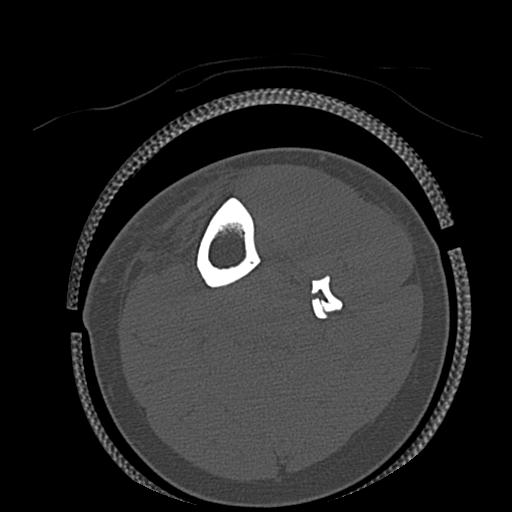

56476 8/28 4R 1/21 2R 左足関節 デジカメ写真 72歳女性 右足関節AS

102755 1/4 2R 1/15 2R 右足関節 68歳女性 右三果脱臼骨折